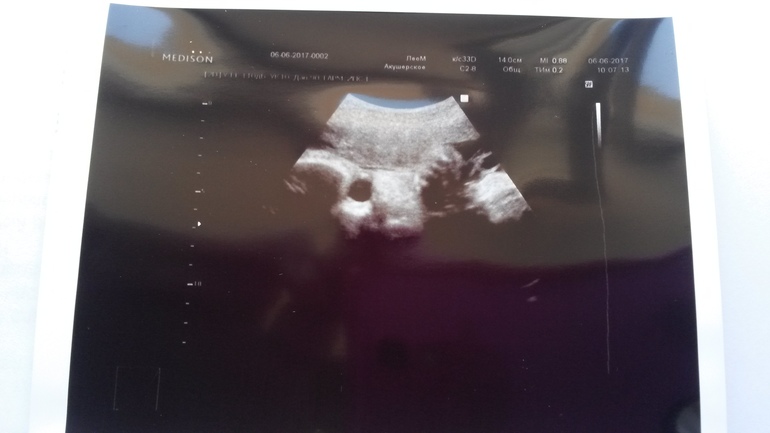

И фото под кат

Это наш глазик,щечка,кулачок,палец которого мы время от времени сосали)))